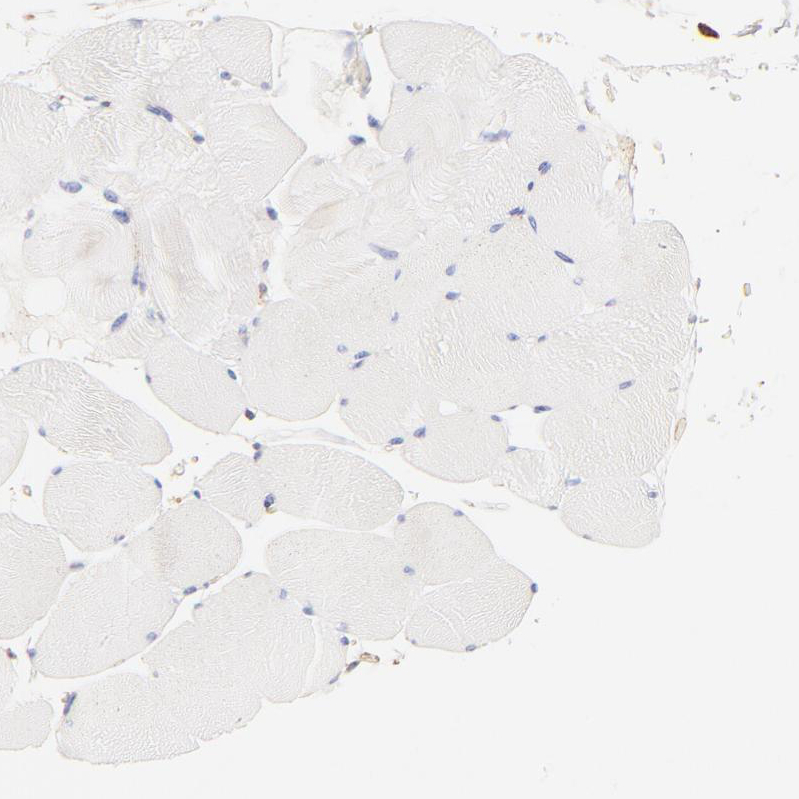

Immunohistochemistry analysis in human prostate and skeletal muscle tissues using HPA002925 antibody. Corresponding FLNA RNA-seq data are presented for the same tissues.